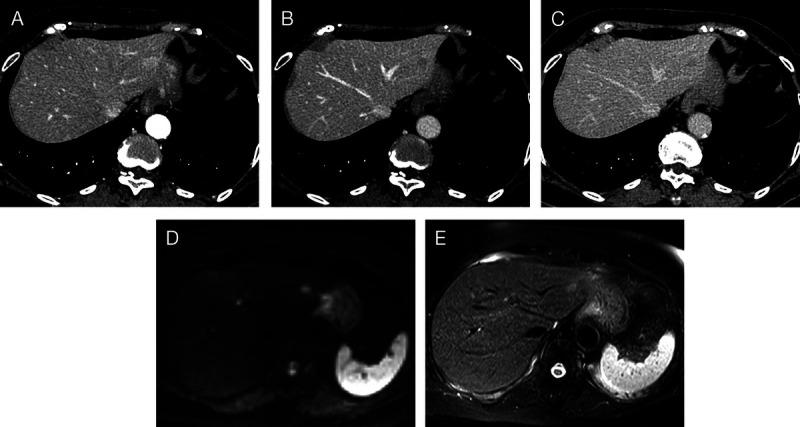

A suspected case of hepatic reactive lymphoid hyperplasia in which EUS-fine needle aspiration contributed to the diagnosis.

Endosc Ultrasound. 2024 Nov-Dec;13(6):379-381. doi: 10.1097/eus.0000000000000092. Epub 2024 Dec 30.